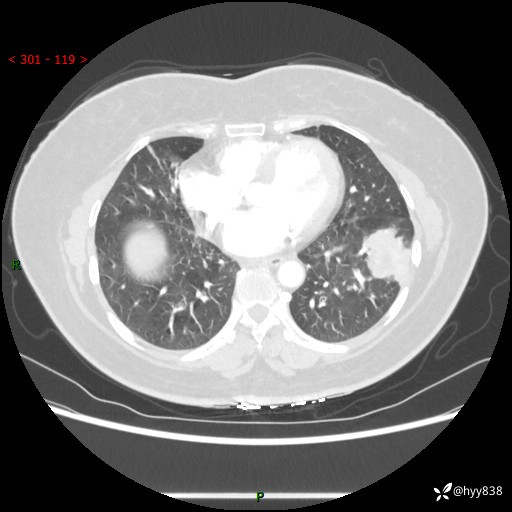

【现病史及既往史】:患者自诉2月前体检发现肺结节(左肺下叶约17mm,右肺上叶4mm),未予特殊处理,2024-10-12当地市第五医院门诊复查胸部CT提示右下肺结节(大小约3.3cm*3.9cm),患者无咳嗽、咳痰,无畏寒、发热、盗汗,无咯血,无胸闷、胸痛、呼吸困难,无恶心、呕吐,无腹痛、腹胀、腹泻等不适,现为求进一步诊治,门诊以“孤立性肺结节”收住我科。 患者本次起病来精神、食欲、睡眠尚可,大小便正常,体力、体重无明显变化。

【检查】:胸部CT增强检查